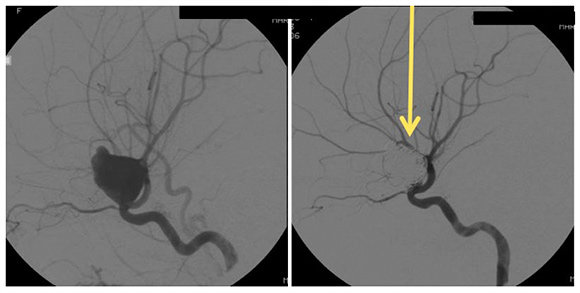

Image shows the remodeling of parent ICA vessel before and after pipeline placement. Arrow points to where the aneurysm used to be.

A braided cylindrical mesh stent designed to divert flow to blind pouches.

- Unlike coiling and liquid embolic agents, the pipeline flow diversion stent is laid across the neck of the aneurysm and does not require intra-aneurysm catheter work.

- Also, unlike the two previous options, the pipeline flow diversion stent causes stagnation of blood within the aneurysm, causing it to shrink, scar down, and remodel the vessel around the stent. This removes the issue of mass effect.